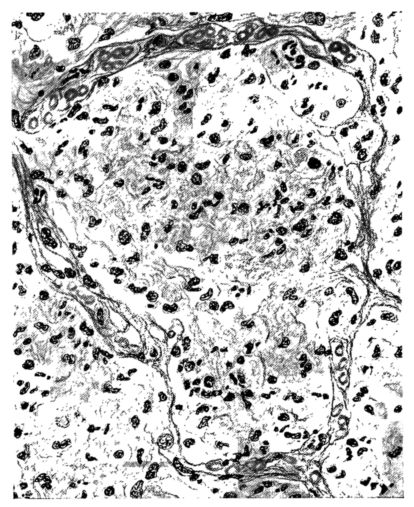

FIG. II. AUTOPSY NO. 98. DRAWING OF A SECTION THROUGH A TRACHEA SHOWING NECROTIZING HEMORRHAGIC INFLAMMATORY PROCESS OF THE MUCOSA.

The changes are less marked, perhaps, in the trachea than in its finer ramifications. The mucosa is constantly more or less destroyed and large areas, usually focal, are entirely devoid of their epithelial covering. This is replaced by a sparse exudate, composed largely of red blood cells, mucus, a small amount of fibrin, and nuclear fragments (Fig. II). It may dip into the submucosa for a short distance, but usually these indentures are associated with the ducts of the mucous glands into which the inflammatory reaction extends. A more striking feature than the exudate, however, is the edema and the congestion of the submucosa. The loose areolar tissue of the submucosa is spread widely apart, and throughout it distended blood vessels are very conspicuous. Occasionally such a vessel is broken and actual hemorrhage appears in the submucosa. Occasionally, too, the inflammation extends down the duct to the mucous gland itself, and here, also, aplastic inflammatory reaction is evident, inasmuch as the acini now stain intensely red with the cells undifferentiated from each other and specked here and there by broken remains of the dead nuclei (Fig. III). After the disease has continued for a short period, even at the end of five or six days, some regeneration of the epithelial lining may be seen (3) (Fig. IV). But despite this, the acute picture persists, and there goes on, side by side, an attempted repair characterized by epithelial regeneration and the same evidence of acute change. Since the lesion is essentially a superficial one, scars or contractures of any extent are not encountered in the trachea, even in examples of the disease that have ended fatally only after many weeks.[4]